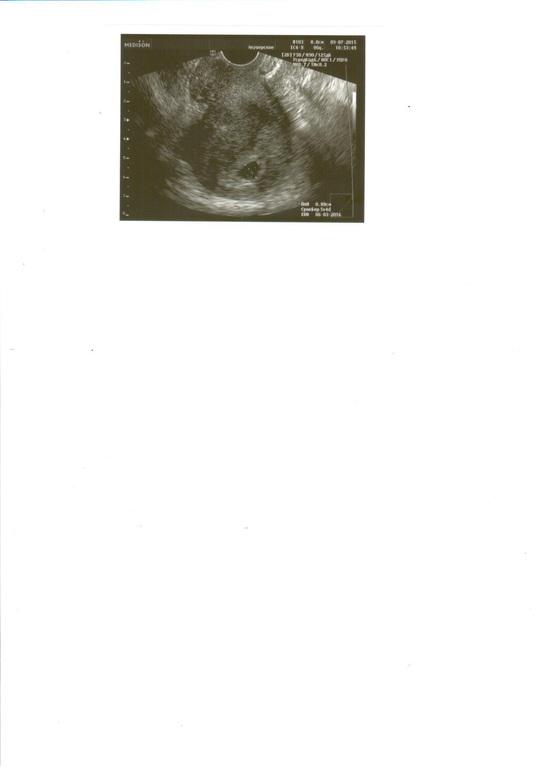

эмбриончик еще не визуализируется, но доктор сказала, что все у меня хорошо и слишком маленький срок! Что-бы я не переживала и приходила слушать сердечко в следующем месяце и даже дала фото моего маленького плодного яичка!!! Я так счастлива. По месячным у меня сегодня 5 недель и 4 дня. А по зачатию говорит 3-4 недели. Девочки, скажите и правда еще рано для эмбриончика??? Фото и результат узи прилагаю!